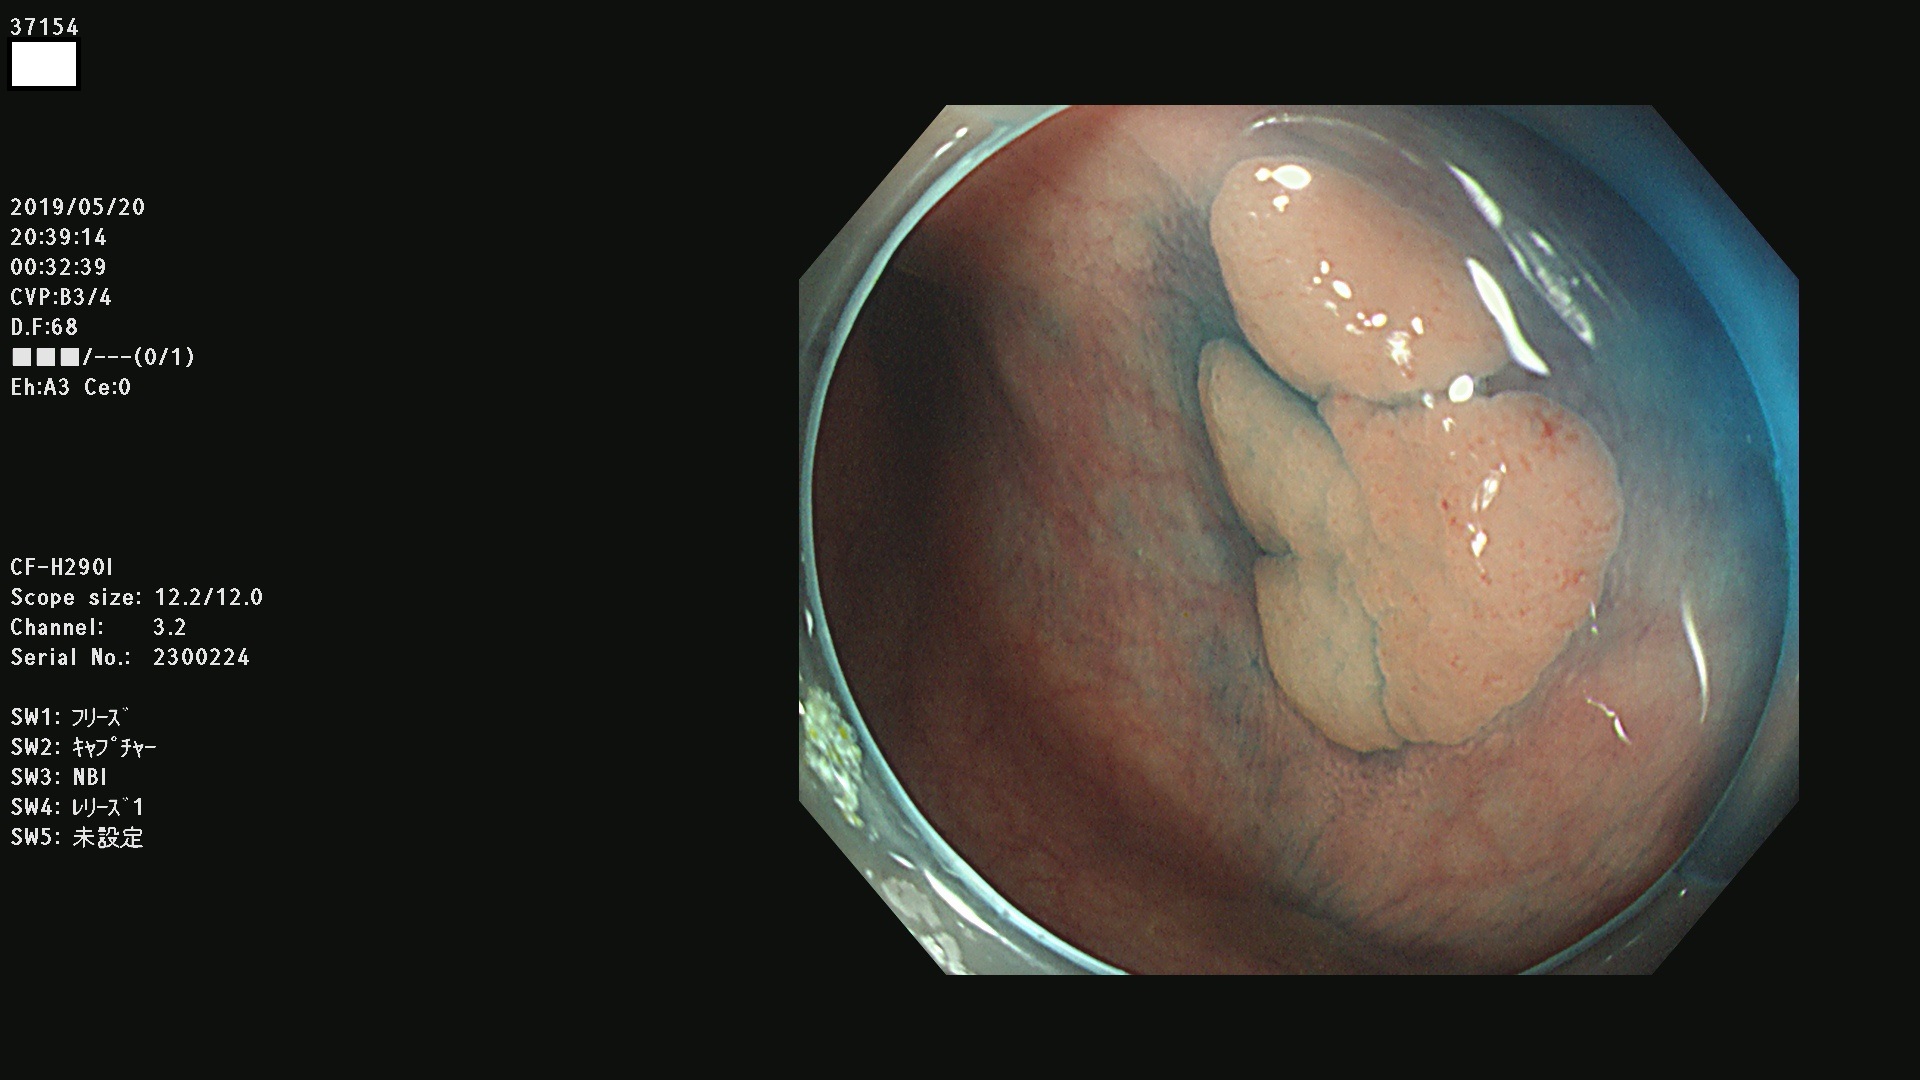

37100 37101 37102 37104 37106 37108 37110 37111 37112 37113 37115 37118(SSAPのみ) 37120 37122 37123 37124 37127(SSAPのみ) 37128(SSAPのみ) 37131 37132 37133 37134 37135 37139 37141 37142 37143 37144(SSAPのみ) 37145 37147(SSAPのみ) 37148 37149 37150 37153 37154 37157 37159 37161 37162 37163 37164 37165 37166 37167 37168 37169 37170 37171 37172 37173 37175(SSAPのみ) 37176 37177 37178 37180(SSAPのみ) 37181 37184 37185 37186 37187 37188 37189 37190 37192 37194 37197 37198

発見困難で危険性の高い平坦型病変(上記100名より抽出)